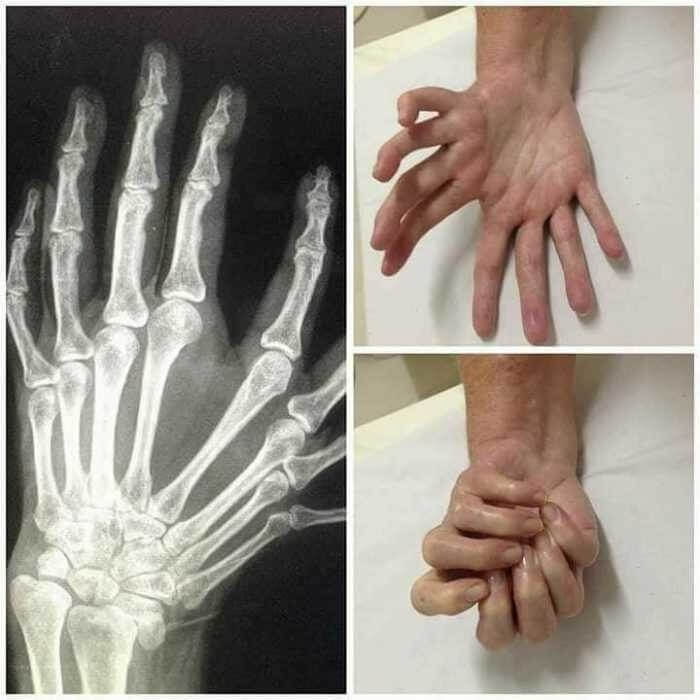

거울-손 증후군은 마치 두 손이 서로 잡고 있는 것처럼 보이게 합니다.

이 증상에 대해서 연구 할 가치가 많은 것은 사실이지만,

가장 흥미로운 사실은, 전 세계적으로

의학 문헌에 보고된 사례가 100 건도 안된다는 것입니다.

이 증상은 '울나르 디멜리아'라 불리는데,

손가락이 여덟 개라는 뜻도 가지고 있어

스스로 손을 맞잡거나 스스로

하이파이브 하는 것 처럼 보인다는 뜻입니다.